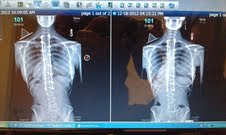

I was a bit nervous going to the doctor this time. Knowing how much I have been up to being back to work and well you know me. If you don’t I am the one who just can’t stop until I sadly over due it. 🙂 Well, the doctor first was pleased that the back was fussing properly and was looking great. BUT, there is always a but, there was some bad news. My heart sank instantly….. take a look at this.

| New shot on left old shot on the right |

Lower Lumbar of the spine starting to curve to the left. This was only another challenge to defeat… I thought to myself. Doctor Klatt mentioned that the back is only being that way because the back is only trying to just find itself again. Doctor Klatt agreed to have me finally start therapy. Therapy will help strengthen my back muscles and stop the other muscles from overcompensating and straining the lower back from bending as you can see.